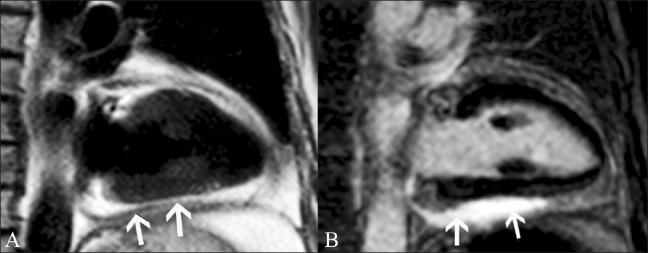

磁共振成像在评估心电图ST段抬高患者中的应用价值。

Utility of magnetic resonance imaging in the evaluation of patients with ST segment elevation on an electrocardiogram.

ST segment elevation is an important electrocardiographic (ECG) change that is typically found in acute myocardial infarction, but may also be seen in a variety of other conditions. MRI plays an important role in the evaluation of these patients. MRI not only establishes the diagnosis, which is essential for appropriate management, but also helps in the assessment of other factors that are important for risk stratification. In this review, we discuss the common and uncommon causes of ST segment elevation and the role of MRI in the evaluation of these disease processes.

摘要